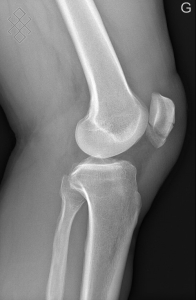

Radiographie du Genou

Positionnement

La durée de l'examen est d'environ 5 minutes.